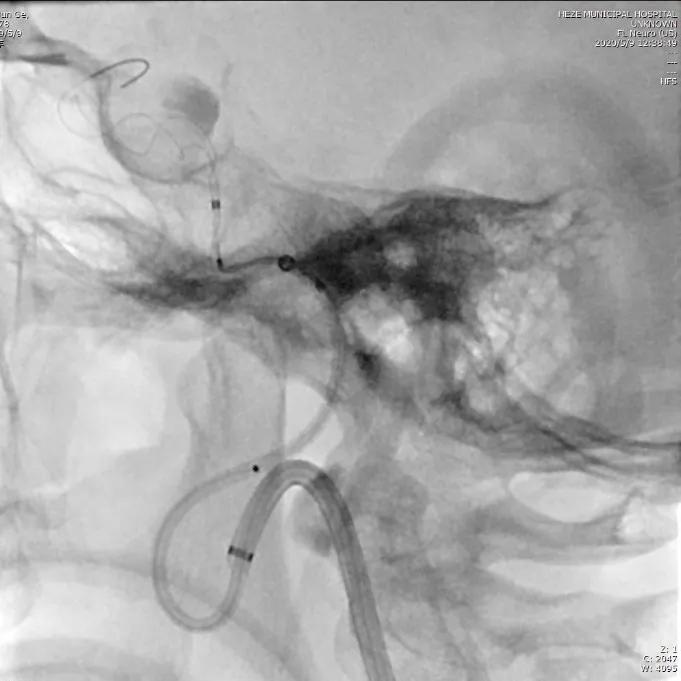

通过导引导管,在TRAXCESS 14微导丝的配合下将T-track微导管置入右侧大脑中动脉。

选择5.0×45mm Tubridge®支架,成功释放,覆盖动脉瘤,造影见动脉瘤腔内造影剂明显滞留。